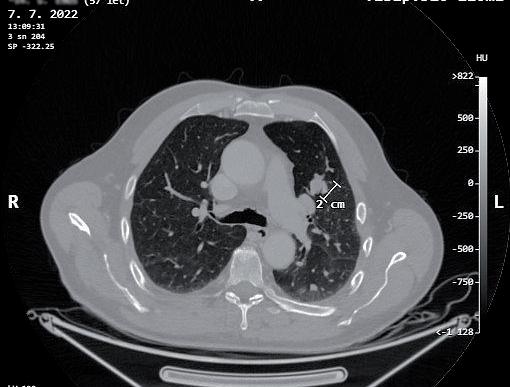

obr. 3.6 Parahilózněně a blízko tepenných struktur hilu lokalizované 2cm metabolicky aktivní ložisko v horním laloku vlevo na CT (a) a PET CT (b) obraze, které se opakovaně paraklinickými metodami nezdařilo mikromorfologicky určit. Bezpečná peroperační biopsie takto umístěného ložiska jeho kompletním vynětím neanatomickou (klínovitou) resekcí je problematická či spíše nemožná videotorakoskopicky i otevřeně

uzlinách. Indikující chirurg je však často v situaci, kdy se primární ložisko v plíci podezřelé z maligního původu nezdařilo verifikovat bronchoskopií s biopsií nebo kar táčkovou cytologií, ani punkční transparietální biopsií pod CT (obr. 3.9, 3.10).